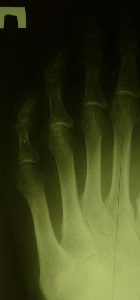

Radiografiile opri pacientul înainte și după intervenția chirurgicală gradul de platfus I

Radiografiile opri înainte și după tratamentul chirurgical al platfus gradul II

Radiografiile opri înainte și după tratamentul chirurgical al III-platfus grad

Radiografiile opri înainte și după tratamentul chirurgical al deformării al cincilea deget

Radiografiile opri înainte și după tratamentul chirurgical al deformarii cauzate de tratamentul greșit al platfus